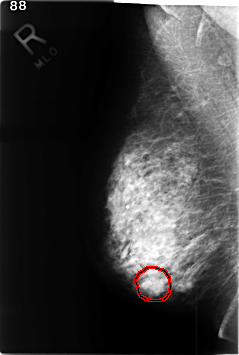

FILE: C_0350_1.RIGHT_CC.OVERLAY

TOTAL_ABNORMALITIES 1

ABNORMALITY 1

LESION_TYPE MASS SHAPE LOBULATED MARGINS ILL_DEFINED

ASSESSMENT 4

SUBTLETY 3

PATHOLOGY MALIGNANT

TOTAL_OUTLINES 1

BOUNDARY